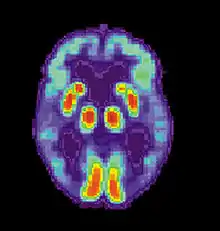

The pursuit rotor task is a simple pure visual-motor tracking test that has consistent results within age groups.[20] This displays a measurement of procedural memory as well as demonstrates the participant's fine motor skills. The pursuit rotor task tests the fine-motor skills which are controlled by the motor cortex illustrated by the green section below.